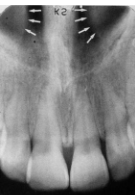

Incisive Foramen

small round radiolucent area between roots of max centrals

(radiolucent)

Superior Foramina of Incisive Canal

two tiny openings on the floor of the nasal cavity

Median Palatal Suture

thin radiolucent line between roots of max centrals

Lateral Fossa

radiolucent area between max canine and lateral (aka canine fossa)

Nasal Cavity/Fossa

large radiolucent area above the max incisors (aka nasal fossa)

Nasal Septum

vertical radiopaque divider in the nasal cavity

(radiopaque)

Floor of Nasal Cavity

dense radiopaque band of bone above the max incisors

Anterior Nasal Spine

v-shaped radiopaque area at base of nasal septum

Inferior Nasal Conchae

diffuse radiopaque projection in the nasal cavity